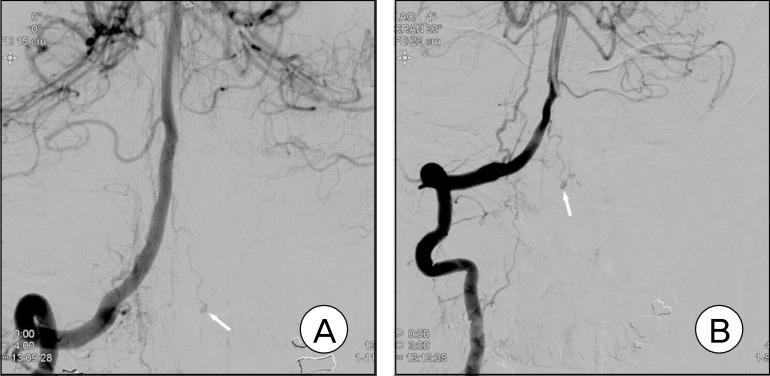

Incidence of aneurysm of the anterior spinal artery is known to be very low and the standard treatment strategy has not yet been established. The author experienced a case of subarachnoid hemorrhage (SAH) caused by the rupture of an aneurysm in the branch of the cervical anterior spinal artery, which was managed conservatively. The patient had end-stage common bile duct cancer and survived for 103 days after onset of the SAH without a re-rupture of the aneurysm.

已知脊髓前动脉动脉瘤的发病率非常低,且尚未确立标准的治疗策略。作者遇到一例由颈段脊髓前动脉分支处动脉瘤破裂引起的蛛网膜下腔出血(SAH)病例,该病例采用保守治疗。患者患有终末期胆总管癌,蛛网膜下腔出血发病后存活了103天,动脉瘤未再次破裂。